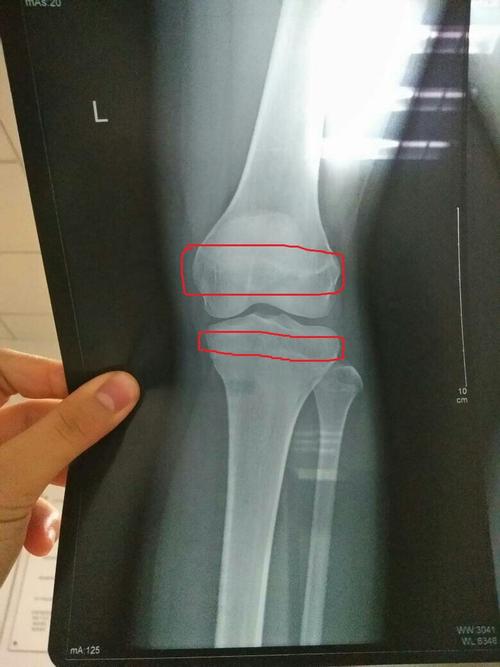

骨骺线在哪

骨骺线在哪,骨骺线在哪个位置图片

请问我今年15 怎么看x光上的骨骺线有没有闭合?

骨骺线在哪个位置图片

骨骺线位置图片

骨骺线图片怎么看

骨骺线接近闭合图

骨骺线

骨骺线图解

骨骺线闭合

骨骺线图片

骨骺线怎么看

骨骺线对照表

骨骺线闭合图

骨骺线对照图

骨骺线闭合区别图

膝盖骨骺线闭合图

骨骺线基本闭合图片

骨骺线的位置示意图